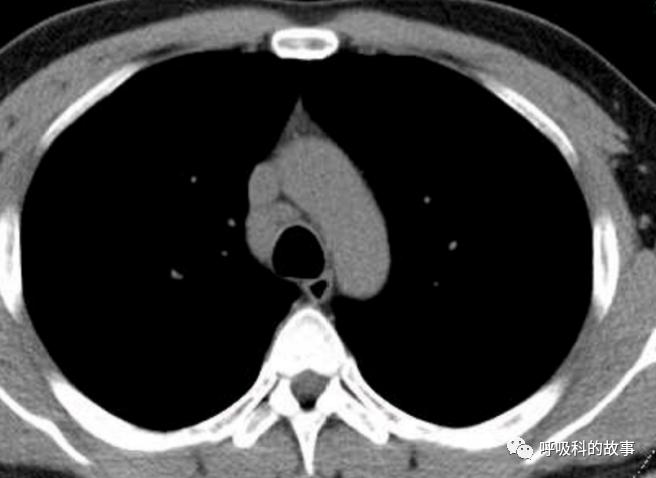

当时我们也曾经考虑给病人做淋巴结活检,但再次遭到患者的拒绝,由于患者体温正常,症状好转,我们也没有坚持。经过了两个多月的伏立康唑治疗,肺部影像基本吸收。

纵隔淋巴结也明显缩小了